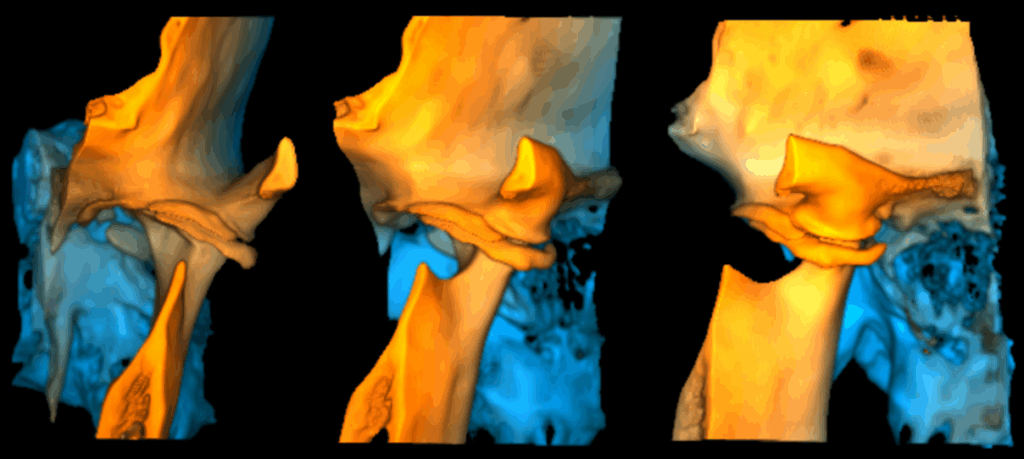

Cortes Sagitales Oblicuos

En la ampliación imagenológica con tomografía computarizada de haz cónico se identifica en el lado derecho se aprecia aplanamiento y esclerosis de la cabeza condilar, con formación de osteofito, presencia de pseudoquiste subcondral y erosión en el contorno superior, además de una disminución del espacio articular en las regiones posterior y lateral. En el lado izquierdo se observa aplanamiento y esclerosis que comprometen la cabeza y el cuello condilar, con osteofito asociado y múltiples cuerpos óseos libres alrededor del cóndilo. Asimismo, se identifica una reducción del espacio articular en las regiones posterior, superior, medial y lateral.

- Condromatosis sinovial de la ATM izquierda.